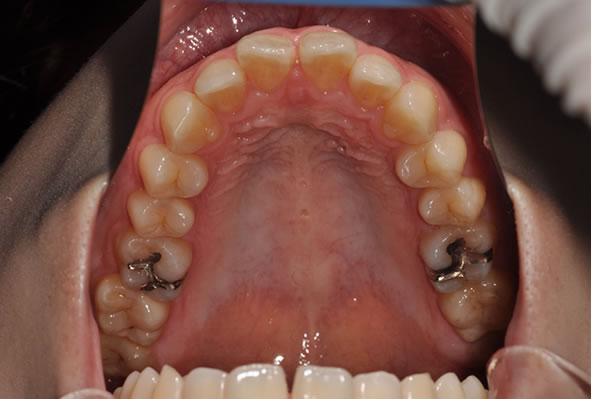

上顎前突症(出っ歯)の矯正症例 ケース01

| 治療前(初診) | 治療後 | |